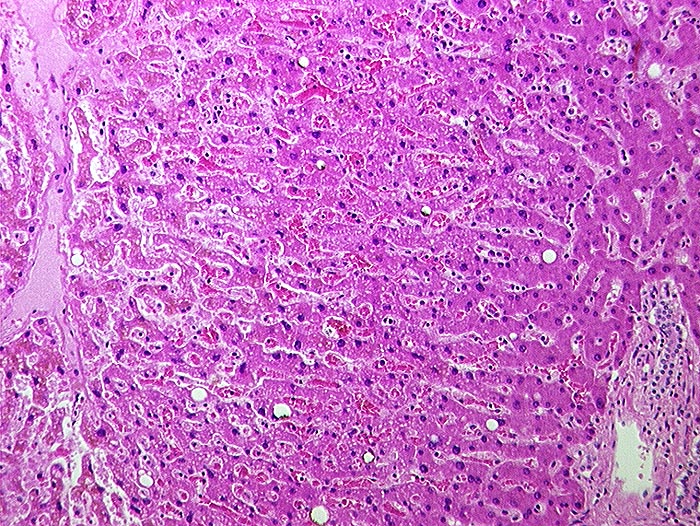

PathoPic – image database / PathoPic ID 1053 - Subakute Stauung

Subakute Stauung

vaskulär / Durchblutungsstörung

Leber

Links eine Zentralvene, rechts ein Portalfeld. Die Sinusoide sind vor allem um die Zentralvene erweitert und die Leberzellplatten leicht verschmälert (Druckatrophie).

In der Bindegewebsfärbung kein vermehrter Fasernachweis rund um die Zentralvene.

Histologie